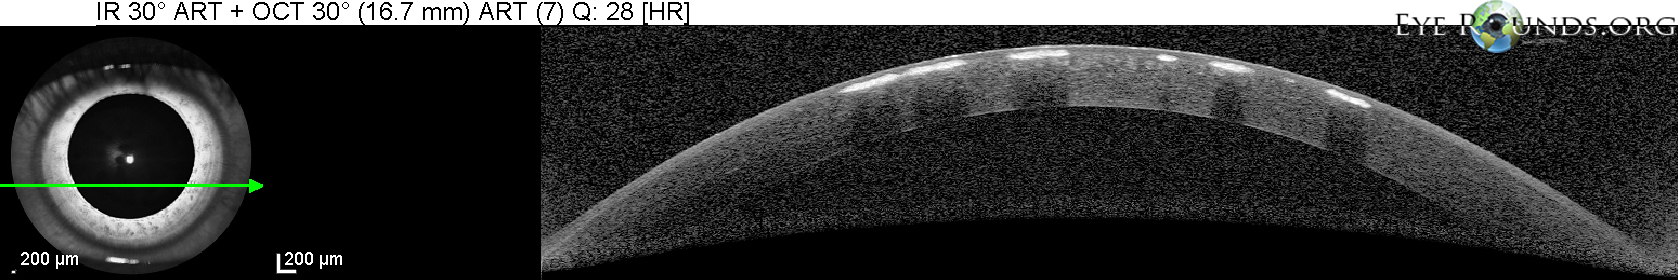

각막의 기질에 빵부스러기, breadcrumb 모양의 흰색의 침착물이 쌓이는데,

이는 각막의 중심부, 기질의 앞쪽쯕에 모이게됩니다.

혼탁의 모양은 둥글며, 병변들의 윤곽이 명확하며

흔히 눈송이, 빵부스러기 등의 모양으로 하고 있으며, 경계가 명확하여,

병변이 진행하면서, 중심부의 혼탁이 융합되어 커지거나, 주변부로 확장될수 있으며,

드물게 병변의 깊이도 깊어져 기질의 뒤쪽으로도 확장되는 경우도 있습니다.